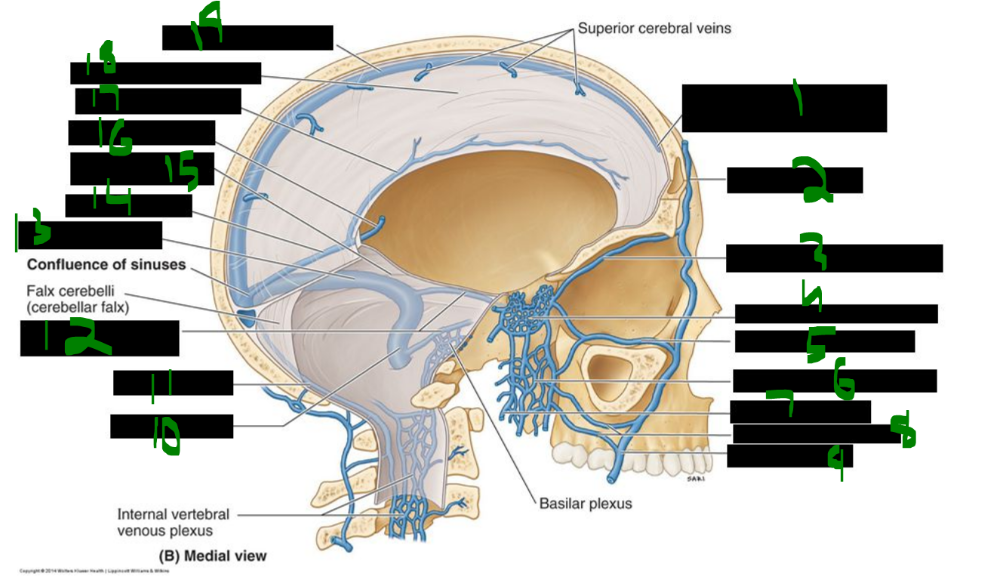

61

The dorsal column pathway carries ______ ______, ______, and ______ sensations, and it crosses in the ______.

discriminative touch, proprioception, vibration, brainstem

62

The anterolateral system, also known as the ______ tract, carries ______ ______, ______, and ______ sensations, and it crosses in the ______ ______.

spinothalamic, crude touch, pain, temperature, spinal cord

63

Both major sensory pathways relay through the ______ before reaching the ______ cortex.

thalamus, sensory

64

from medial to lateral, describe the sensory cortex humunculus:

______ , ______ , ______ , ______ , ______ , ______

______ , ______ , ______

______

genitals, leg, hip, trunk, neck, head

arm, elbow, forearm, hand, fingers, thumb

eye, nose, face, lips, teeth, gums

jaw, tongue, pharynx

abdomen

65

An injury to the corticospinal system (pyramidal tract) ______ the pyramidal decussation results in ______ paralysis.

above, contralateral

66

An injury to the corticospinal system ______ the pyramidal decussation results in ______ paralysis ______ the lesion.

below, ipsilateral, below